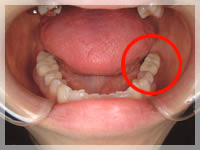

【before】

【after】